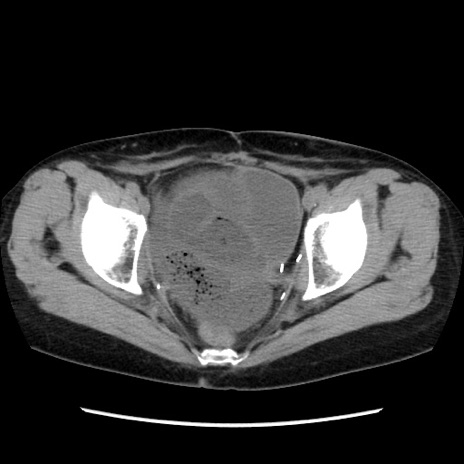

症例32(横断像)

【症例】40歳代 女性

【主訴】上腹部痛、嘔気・嘔吐

【現病歴】約9時間前頃から急に上腹部痛、嘔気、嘔吐が出現。改善しないため救急要請。

【既往歴】子宮頚癌(広汎子宮全摘術、放射線療法)、腸閉塞

【身体所見】腹部:平坦、軟、腸雑音亢進、上腹部を中心に腹部全体に圧痛あり。

【データ】WBC 8400、CRP 0.03